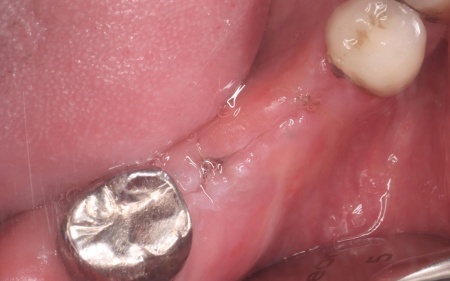

60代男性 根が割れた歯を抜歯してインプラント治療を施した症例

定期健診で通院されていた患者様より「右下の歯ぐきが腫れてきた」とご相談いただきました。

拝見したところ、右下の奥歯周辺の歯ぐきが腫れていました。

歯やあごの骨の状態を詳しく調べるためレントゲン検査を行った結果、右下の奥歯2本(第2小臼歯、第1大臼歯)は、歯根が縦方向に割れている可能性が高いと考えられました。

そこで歯ぐきの一部を開き内部を直接確認したところ、いずれの歯根が垂直方向に割れていました。

以上のことから、歯を温存することは難しいため抜歯が必要と診断しました。